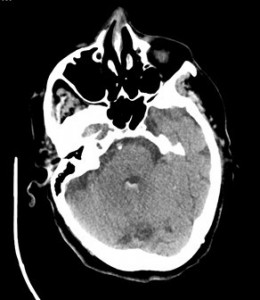

Explicación: Ante un código ictus se debe realizar siempre de entrada un TC sin contraste. Es la primera técnica de elección, tiene una sensibilidad próxima al 100%. La TC permite diferenciar con gran precisión un ictus isquémico de uno hemorrágico y descartar la presencia de lesiones intracraneales de origen no vascular causantes del cuadro ictal, como tumores o hematomas subdurales.

Se identifica una lesión hiperdensa de morfología redondeada en el tálamo izquierdo, con edema en su periferia y extensión a los ventriculos tercero y cuarto.

¿CUÁL ES EL DIAGNÓSTICO MÁS PROBABLE?